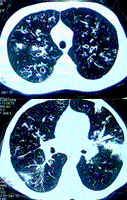

实验室检查:WBC11.1×109/L(正常值4.0×109~10.0×109/L),NEU51.9%(50%~75%),Hb145g/L(男120~165g/L),血小板(Plt)334×109/L(100×109~350×109/L);血沉(ESR)49mm/1h(男<15mm/1h),C反应蛋白(CRP)11.5mg/L(正常值﹤8mg/L)。血免疫球蛋白定量(Ig):IgG28.0g/L(7~17g/L)、IgA3.91g/L(0.7~3.8g/L),IgM3.26g/L(0.6~2.5g/L),T细胞亚群:淋巴细胞数目大致正常,CD4+/CD8+比例倒置。免疫指标大致正常。肺功能提示为阻塞性通气功能障碍:1秒钟用力呼气量占预计值百分数(FEV1%pred)27.6%Pred,用力肺活量59.1%Pred,1秒率50.2%Pred,可逆试验(-),残气量3.68L,363.6%Pred,肺总量5.73L,135.5%Pred,残总比64.18%,弥散量63.3%Pred.胸部高分辨CT(HRCT,见图1、2):双肺可见支气管扩张,伴肺内渗出斑片影。粪便苏丹Ⅲ染色(+);血白蛋白(ALB)32g/L(35~51g/L),丙型肝炎病毒抗体(HCV-Ab)(+);腹部B超:肝剑下4.0cm,肋下3.1cm,肝回声增粗欠均匀,可见条索样回声,提示肝弥漫性病变。